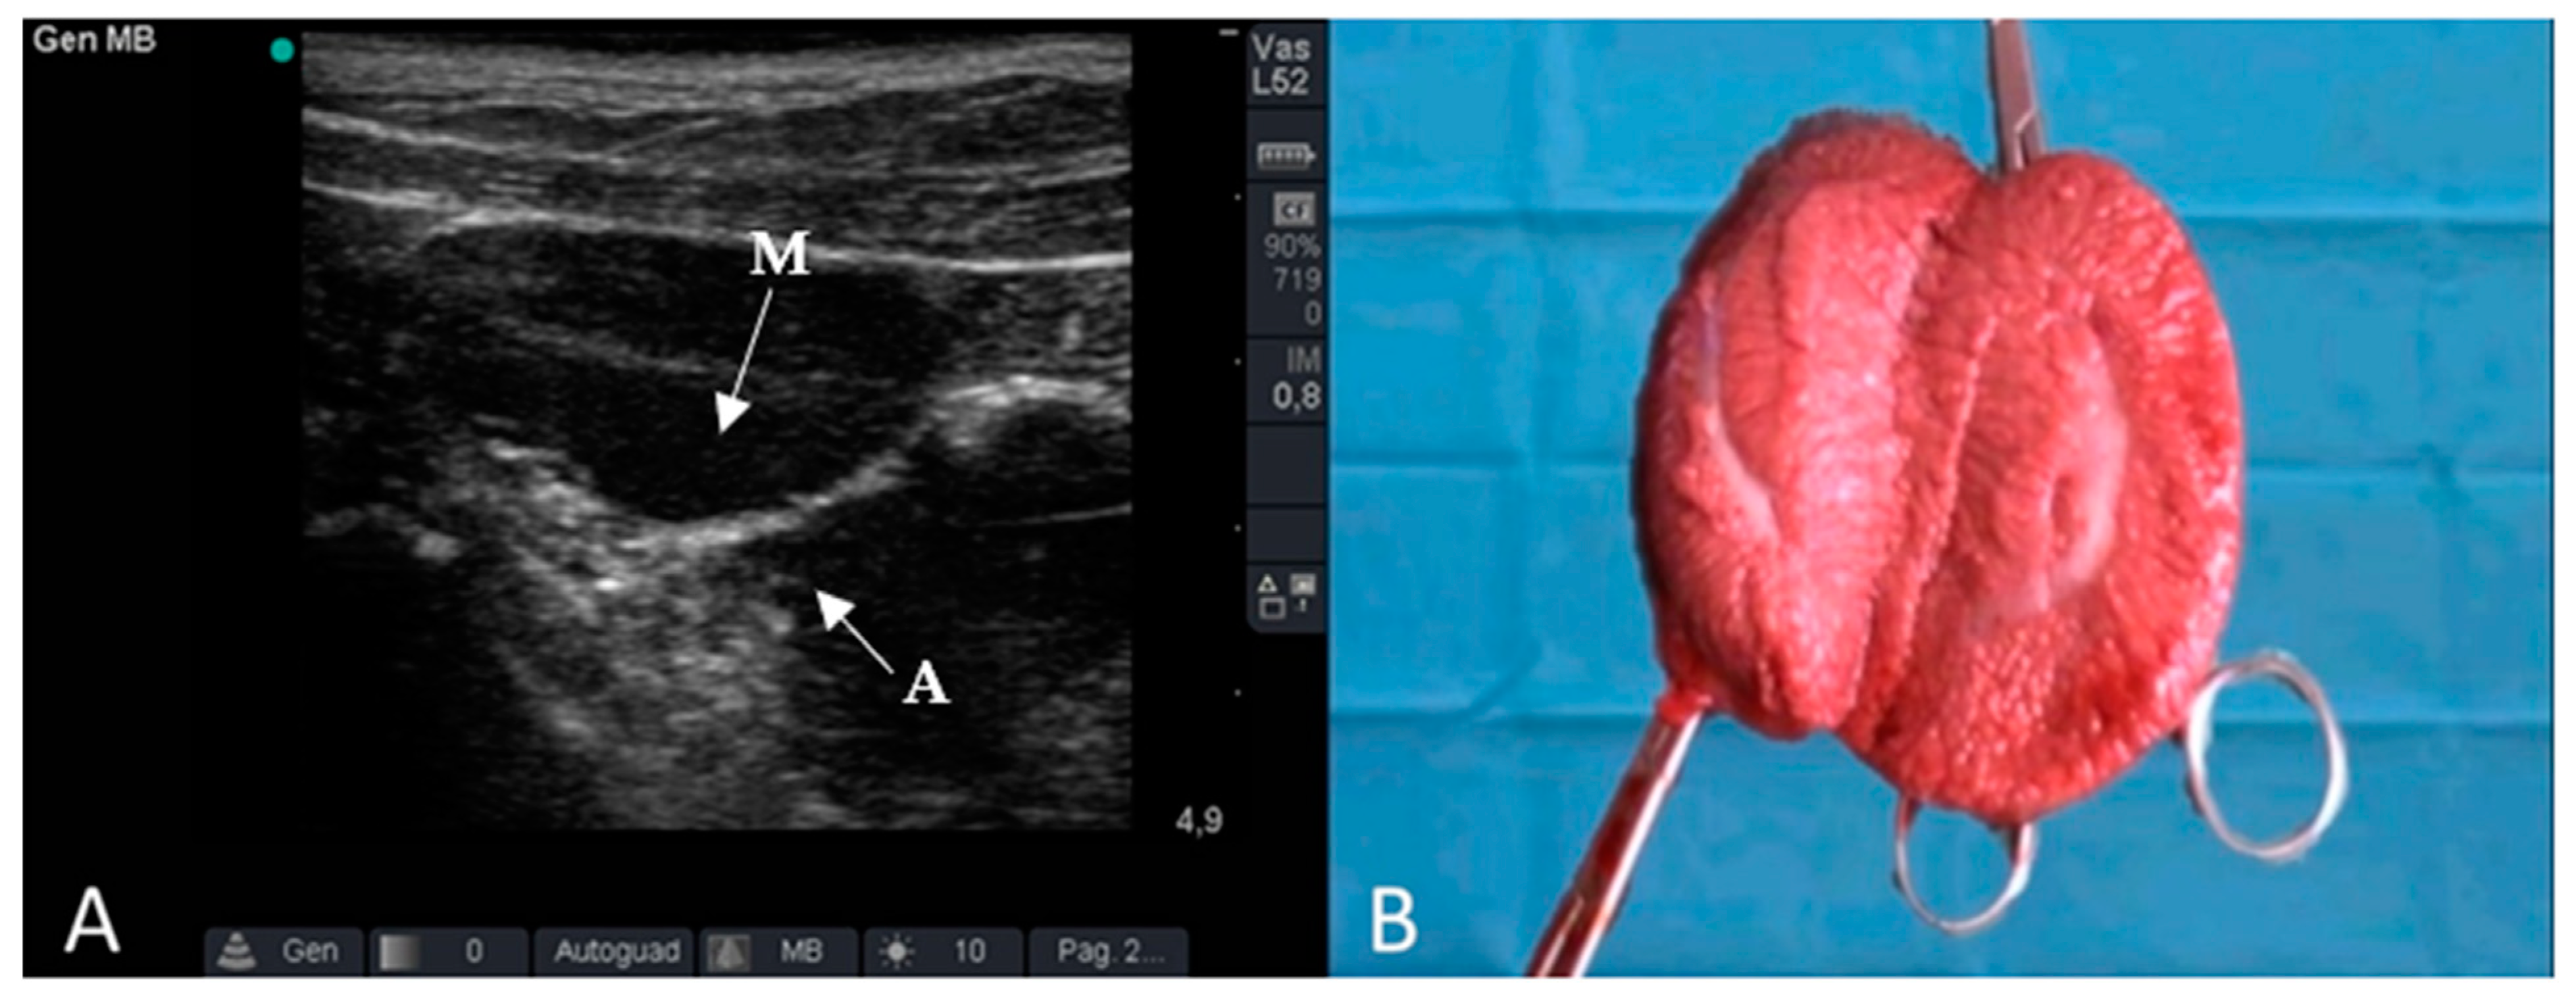

2.3. Ultrasound Examination

2.4. Surgical Approach

3. Results